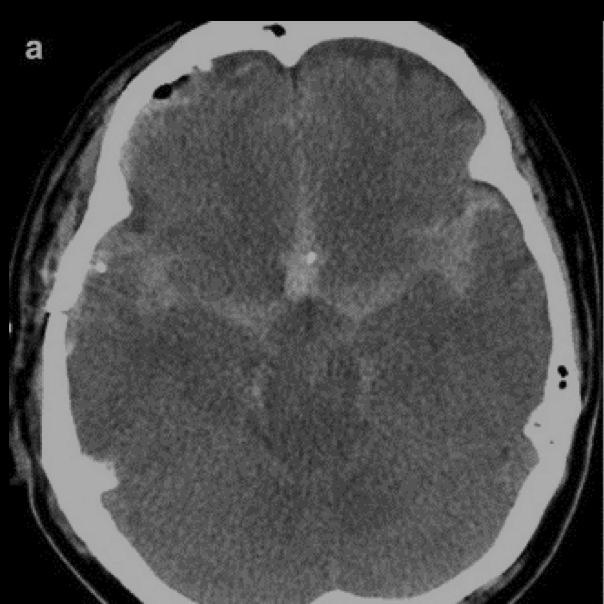

7

Q

Que es?

A

EVC isquemico subagudo